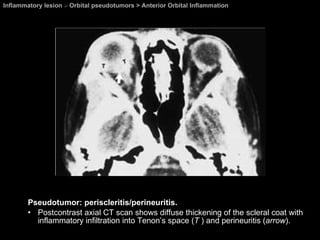

Anterior Orbital Inflammation Orbital pseudotumors  Inflammation involves the anterior orbit and adjacent globe. Pain, proptosis, lid swelling, and decreased vision.  Extraocular muscle (EOM) motility is usually unaffected.

Anterior Orbital Inflammation Orbital pseudotumors  CT and MR imaging   Thickening of the uveal-scleral rim with obscuration of the optic nerve junction, which enhances with contrast infusion on CT.

Inflammatory lesion  >  Orbital pseudotumors > Anterior Orbital Inflammation Pseudotumor: periscleritis/perineuritis. Postcontrast axial CT scan shows diffuse thickening of the scleral coat with inflammatory infiltration into Tenon’s space ( T  ) and perineuritis ( arrow ).